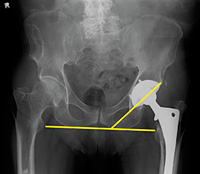

Figure 1: Angle of inclination 40o +/- 10°.

The position of the acetabular component and the stem can be easily assessed on an AP view. The acetabular angle of inclination should be 40 degrees +/- 10 degrees. (Figure 1) Anteversion cannot be assessed on the AP and a frog leg view is very difficult to obtain in these patients, so CT is often used to assess this angle. The center of rotation, however, can be assessed on the AP view. (Figure 2)